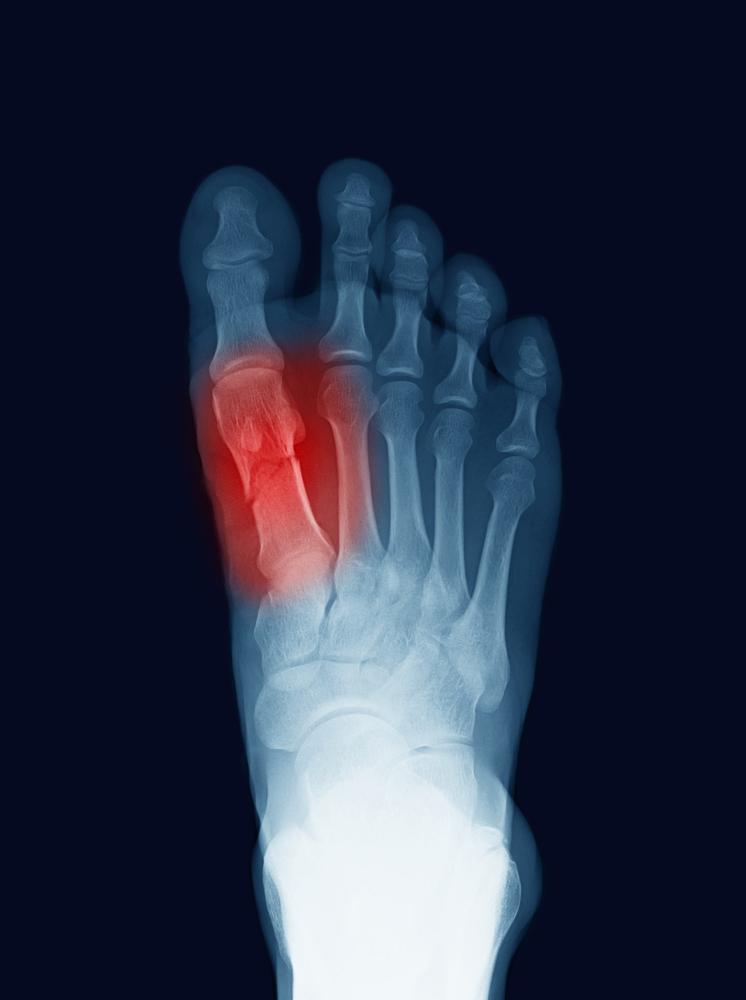

Les fractures du pied ou de la cheville sont fréquentes. Nos podiatres sont habituées de faire la prise en charge : radiographie, immobilisation, radiographie de suivi et protocole de réhabilitation par la suite.

Utile pour vérifier s'il y a fracture, calcification, dépôt calcaires, et bien plus.